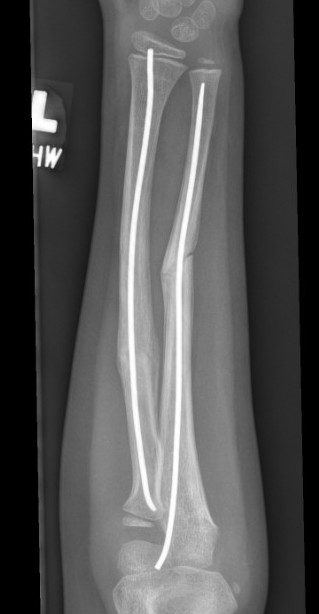

3. Intramedullary elastic nail

TENS technique

Technique

Radius (typically first as more difficult to reduce)

Entry point with awl 2 cm proximal to distal physis

1. Radial styloid / distal lateral entry

- ensure radial nerve / cephalic vein, 1st extensor compartment protected

2. Listers tubercle / dorsal entry

Elastic Nail size

60 - 70% of the intramedullary canal

Typically 1.5 - 2.5 mm

Fracture reduction

Avoid passing nails incorrectly multiple times as may cause compartment syndrome

Bend tip of elastic nail

May need small open reduction

Cut nail

Withdraw 1 cm, cut with endcutter, then advance

Ulna (usually reduced after radius fixation)

Entry point 2 cm distal to apophyseal plate

1. Proximal lateral

- avoids ulna nerve

3. Distal medial

Postoperative

Cast in supination to tighten interosseous membrane

Cast 6 weeks

Removal of TENS at 4 - 6 months once osseous union established